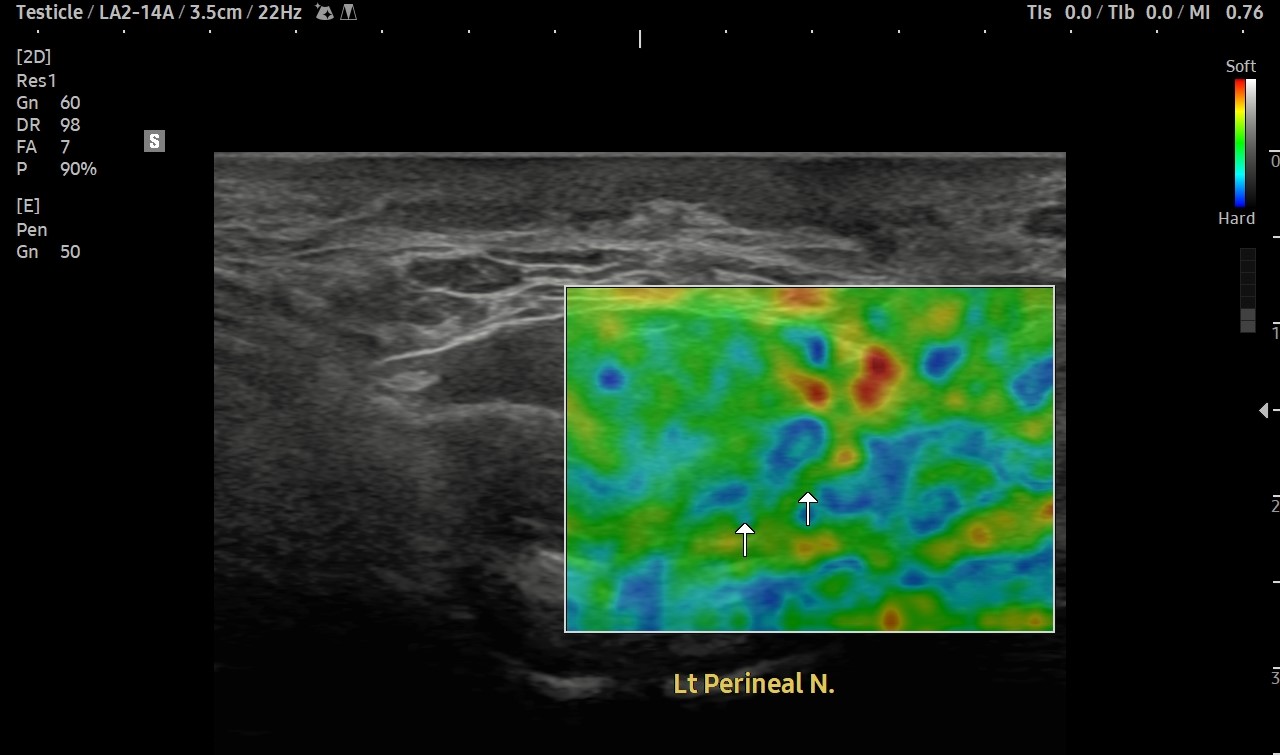

[치료 전]

[치료 후]

- 치료횟수 : 40 회